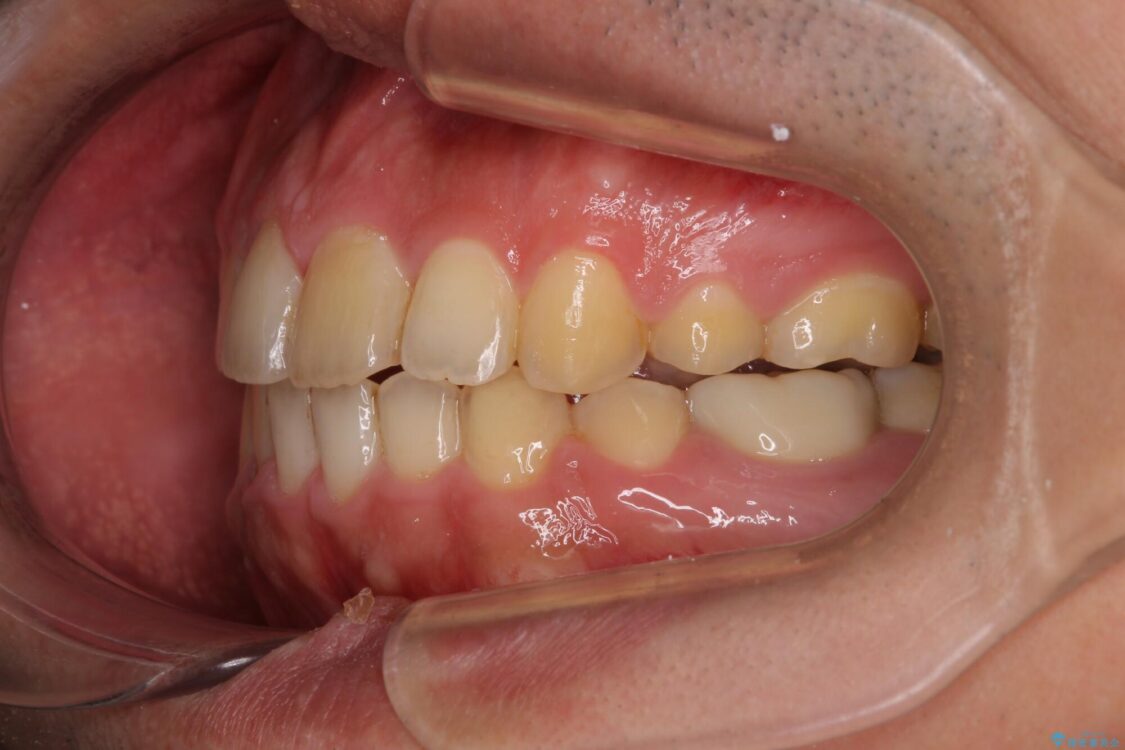

高校時代に行った抜歯矯正が後戻りをしたとのことで来院された患者様です。

治療前

• 後戻りでデコボコの前歯 インビザライン矯正治療 治療前画像